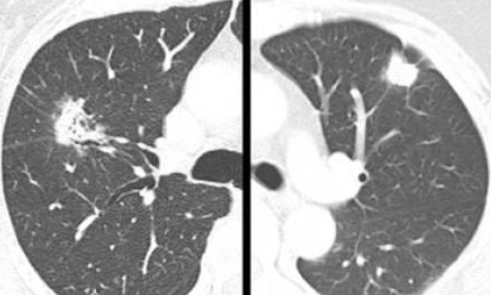

首先我们必须明确诊断,在这方面薄层CT扫描具有非常重要的地位,经验丰富的影像学医师的建议对治疗方案的选择几乎起决定性作用而不可忽视,一般情况下影像科医师根据薄层CT及重建90%以上的患者能够判断良恶性,对于良性结节应采取观察原则,无论手术、放疗、消融都不建议! 对于恶性结节,.........[详情]关键词:肺,结节,及,早期,癌的,诊断,、,治疗原则,首先,